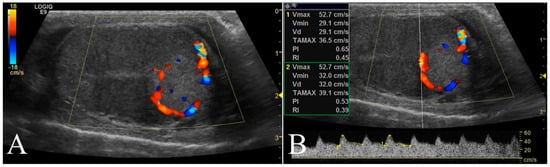

Longitudinal and transverse views were obtained from each testis using B-mode. B-Mode ultrasound parameters included anatomical site of affected testicle (scrotal or abdominal), maximal diameter (cm), location (left, right, or both testicle), margins (regular, irregular), echogenicity (hyperechoic, hypoechoic, isoechoic, anechoic or mixed), and echotexture (homogeneous or inhomogeneous) of the lesions relative to normal surrounding (or contralateral, in the case of a diffuse lesion) testicular parenchyma (Figure 1).

Figure 1. Representative B-Mode ultrasonography scans. (A) Left testis of a 11 year old mixed breed dog with a focal hyperechoic nodule (seminoma) characterized by homogenous echotexture and regular margin. (B) Mixed cell tumor (leydig and seminoma) recorded as two nodular lesions in the right testis of a 13 year old Epagneul Breton. The lesions had mixed patterns, inhomogeneous echotextures and irregular margins.